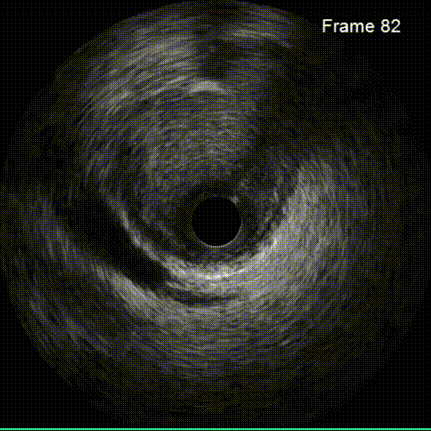

患者全麻后,右侧股动脉建立主入路,主动脉根部造影显示主动脉瓣无明显钙化。心室内轻中量反流,主动脉及心脏情况整体较为稳定,根据术前策略预装23mm瓣膜。超硬置入左心室后,因超硬压迫无冠瓣叶导致急性反流,病人血压降至40mmHg,遂迅速将输送器送入主动脉根部,快速释放瓣膜后,病人血压恢复至正常。瓣膜脱钩后造影显示左冠开口存在一定狭窄,IVUS评估左冠开口狭窄约60%,符合PCI指征,植入开窗支架改善狭窄,最终再次造影加IVUS评估左冠开口,确定狭窄解除。

IVUS探查左冠开口狭窄60%

放置开窗支架

球囊后扩支架

对于具有冠脉高风险的患者需要选用合适的球囊在预扩阶段充分评估瓣叶推移情况,预估瓣膜植入风险;对于瓣膜,需要选择具有收腰设计的瓣膜,以避免瓣架将瓣叶完全推移。除了TAVR手术球囊瓣膜选择外,对于冠脉的评估也至关重要。随着血管内超声在优化PCI手术逐渐的普及,尤其在左主干病变中发挥着愈发重要的作用,我们医院也将IVUS在左主干病变中的心得应用在TAVR术中冠脉阻挡高风险的患者中,更加精准的评估瓣膜植入后左主干开口的受累情况。若发现左主干开口狭窄,需采取开窗支架技术,保障左主干开口血流关注,冠脉支架植入后仍需IVUS评估冠脉支架的贴壁、左主干开口以及冠脉支架与假体瓣膜之间的相互关系。